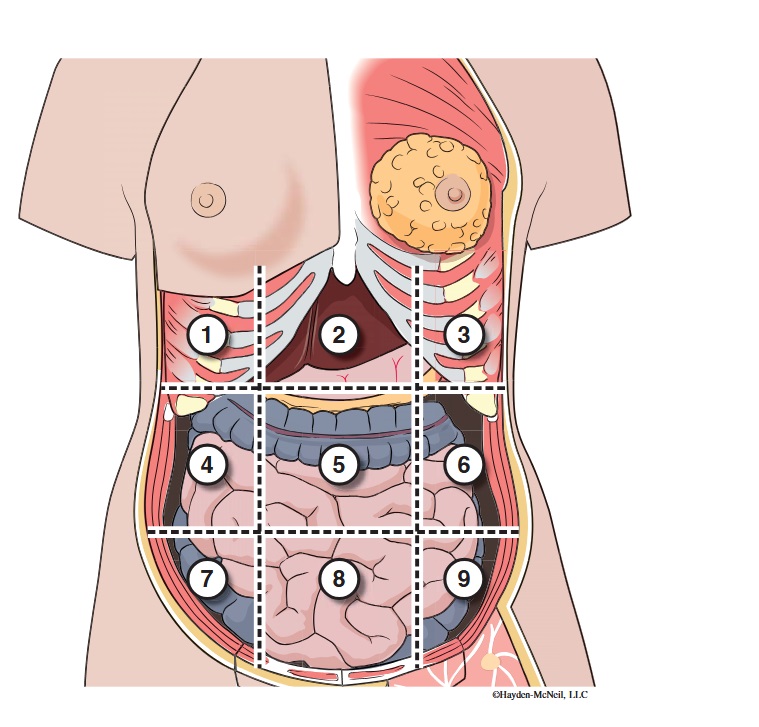

What abdominal region is labeled #1?

right hypochondriac

What abdominal region is labeled #2?

epigastric

What abdominal region is labeled #3?

left hypochondriac

What abdominal region is labeled #4?

right lumbar

What abdominal region is labeled #5?

umbilical

What abdominal region is labeled #6?

left lumbar

What abdominal region is labeled #7?

right iliac/ inguinal

What abdominal region is labeled #8?

hypogastric

What abdominal region is labeled #9?

left illiac/ inguinal

What organs are apart of the right hypochrondriac region?

right lobe of liver, gallbladder, right adrenal gland

What organs are apart of the epigastric region?

pyloric end of stomach, duodenum, pancreas

What organs are apart of the left hypochondriac region?

stomach, spleen, left adrenal gland

What organs are apart of the right lumbar region?

ascending colon, right kidney, portion of small intestine

What organs are apart of the umbilical region?

omentum, mesentery, small intestine

What organs are apart of the left lumbar region?

descending colon, left kidney, portion of the small intestine

What organs are apart of the right iliac/ inguinal region?

cecum of large intestines, appendix, right ovary

What organs are apart of the hypogastric region?

ileum, bladder, uterus

What organs are apart of the left iliac/ inguinal region?

sigmoid colon, left ureter, left ovary